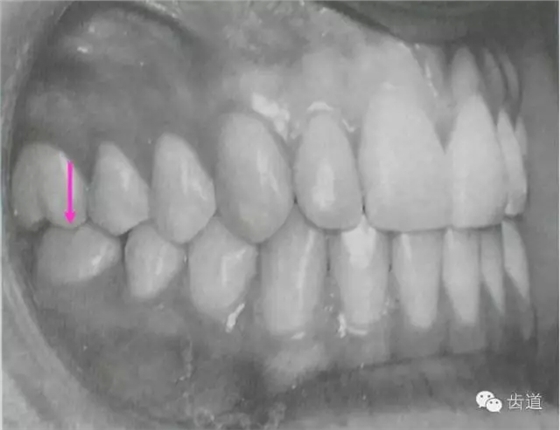

上、下牙弓密切而穩(wěn)定的咬合接觸關系,使得牙齒在各種生長發(fā)育動力作用下,得以保持正常的萌出高度,如果缺少對頜牙,則牙齒將過度萌出,直至遇到萌出阻力(如對頜牙槽骨等)為止;如果因間隙過小,牙萌出受阻,萌出時阻力大于萌出力,則該牙將低位萌出或阻生。